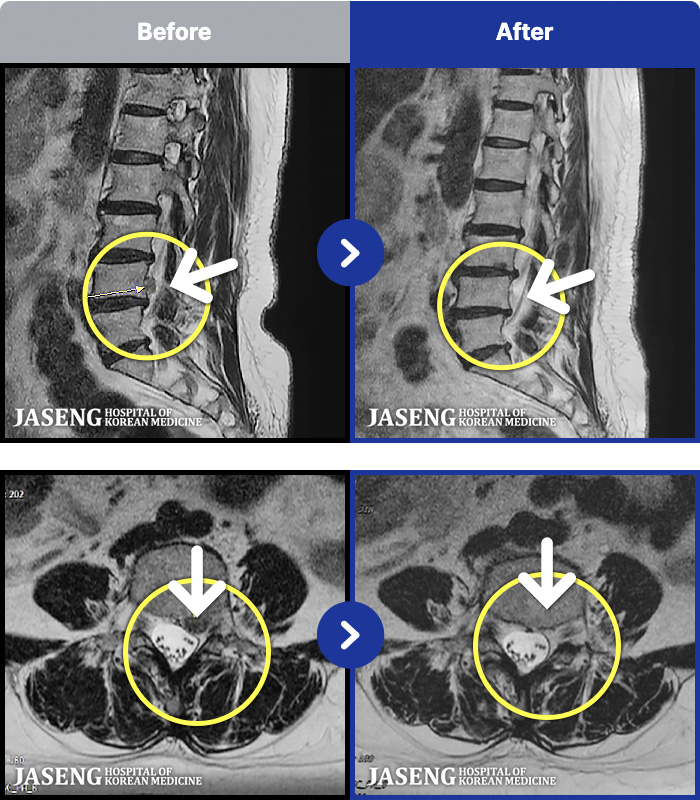

ȯںп Ǹ ǿ ԿǾ, ο ġ ۿ Ƿ ġḦ Ͻñ ٶϴ.